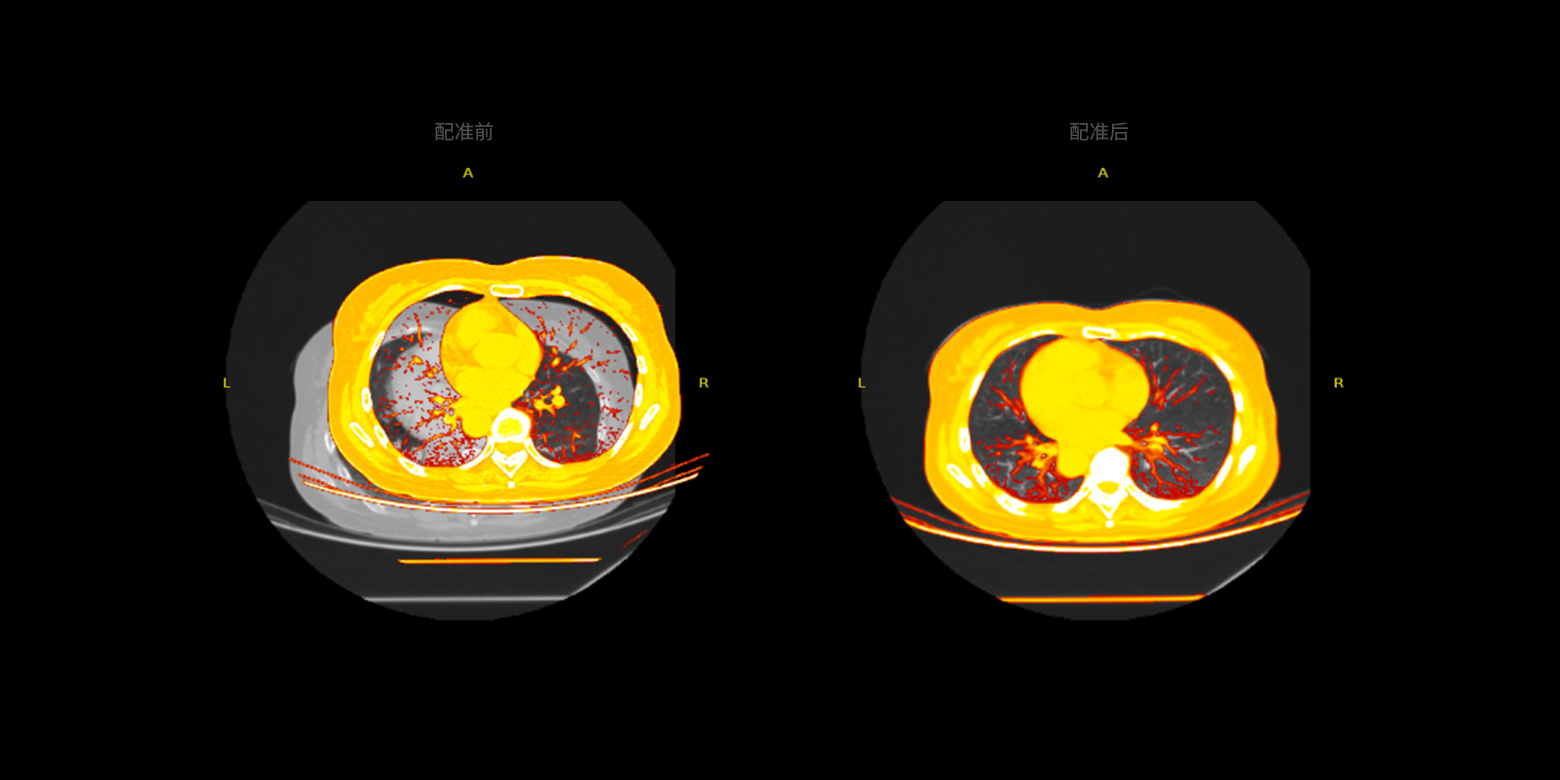

多模式的數據配準

提供多模式的數據配準,可融合不同模式或不同序列的圖像數據,例如同一(器官)部位的CT、MRI、PET數據配準,進而精準地對病灶作定性或定量的風險分析。